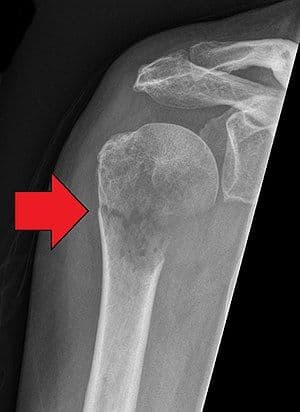

Impacted Fracture - एखादे हाड तुटते तेव्हा त्या हाडाचा हिस्सा दुसऱ्या हाडांमध्ये घुसण्याची स्थिती.

Pathological Fracture - आजारामुळे हाडे कमजोर होऊन तुटणे.